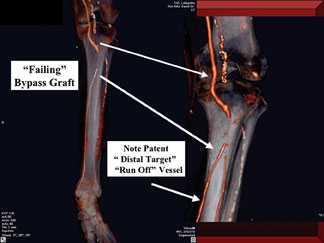

Most patients with diabetes who do suffer from severe infrapopliteal CTOs have the phenomenon of “pedal sparring.” This refers to the fact that the dorsalis pedis artery (DPA) and/or posterior tibial artery (PTA) below the level of the ankle will often be free of obliterative disease. These arteries are patent and be perfused by a collateral artery network, revealing a “distal vascular target” appropriate for revascularization. This presents an opportunity for either surgical or endovascular revascularization.

This becomes very important with committed limb salvage angiography and during CTA. If physicians are not aware of this “pedal sparring,” they will not consider revascularization and their imaging will be inadequate. Patients often receive referrals for primary amputation when they actually have the potential for revascularization.